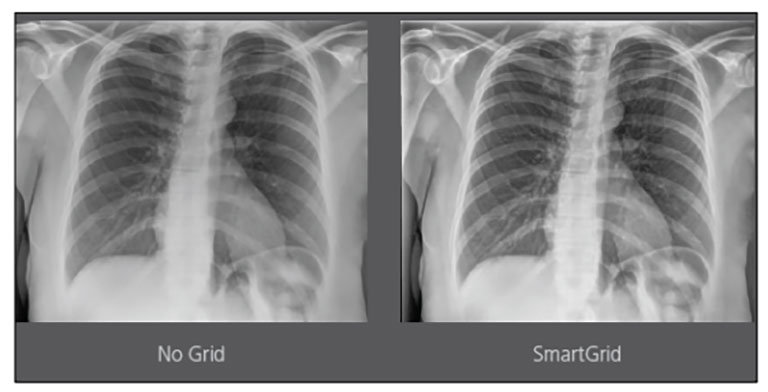

Upgrading your imaging system to a solution designed for outstanding image quality is no longer out of reach — it's now easier, more affordable, and more effective than ever before.

Our Carestream Focus HD 35/43 Retrofit Detectors, powered by Image Suite Software, are an ideal solution to step up to full digital X-ray for customers who simply cannot compromise on image quality. It seamlessly integrates into existing setups, bringing the power of full digital X-ray with minimal disruption and maximum clarity, along with the following benefits: